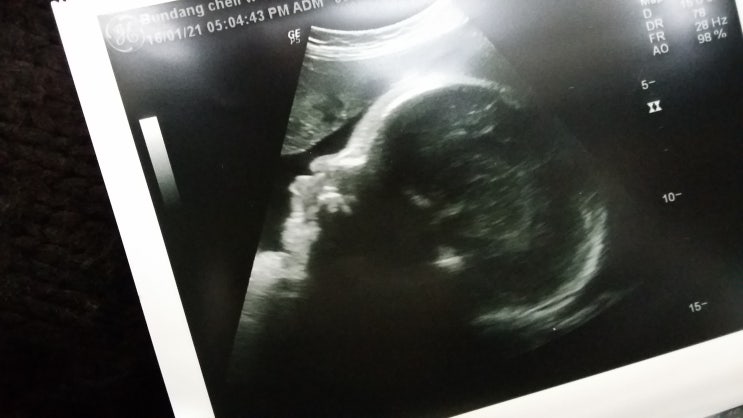

열번째-열세번째만남.임신 33-37주차

열번째만남 2015.12.26 임신 33주차. 8개월 몸무게변화 4주전 +2.2키로 (56.2 ㅡ> 58.4) 임신시작...